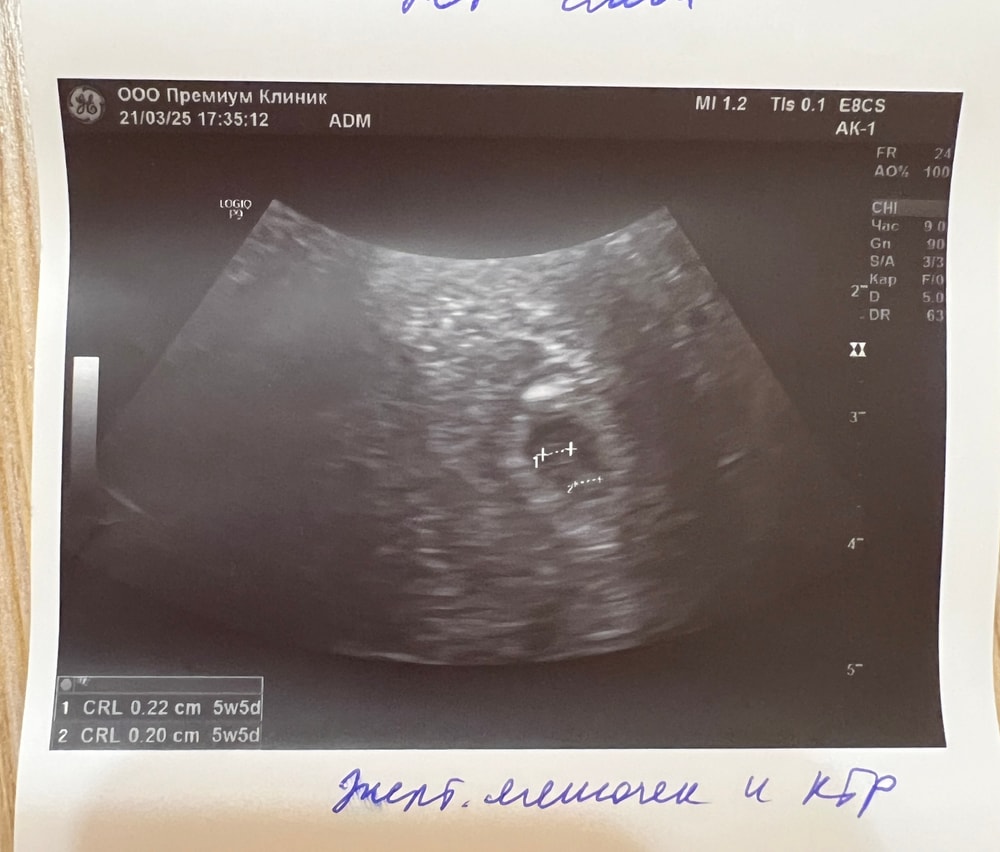

сегодня показало СВД 6.2 мм, ктр и жм 2,2 мм